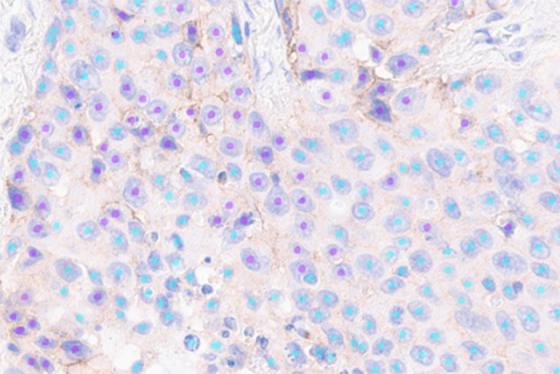

Lunit SCOPE is an Artificial Intelligence (AI)-based digital pathology image analysis software that empower pathologists to improve accuracy, scoring agreement, and workflow efficiency. Lunit SCOPE PD-L1 assists in the detection and quantification of PD-L1 expression in NSCLC tissue stained with PD-L1 22C3 pharmDx assay.

Assay: PD-L1 IHC 22C3 pharmDx

Tissue Type: NSCLC

Scoring: TPS